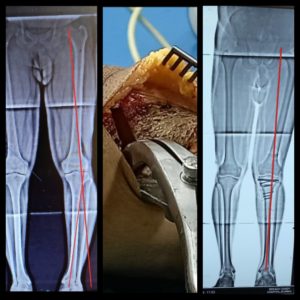

History: 41-yr-old man was suffering from immense pain in his left knee and standing scanogram showed a varus malalignment whereas MRI showed a medial meniscus tear.

Case: A plain arthroscopic meniscectomy would not have relieved his symptoms. Normal mechanical axis is the line from the center of head passing through the lateral tibial spine in the knee and comes to lie in the center of the ankle. Look at the preoperation scanogram, the line is way outside the ankle. An open wedge osteotomy was done along with arthroscopic meniscectomy and the alignment of the limb was restored. Look at the mechanical axis from center of femoral head to center of knee and center of ankle. Open Wedge High Tibial Osteotomy is a forgotten art but it is reviving again now with better implants so that patient can bear weight early. Knee movements have started for this patient and weight-bearing will commence in 3 weeks.